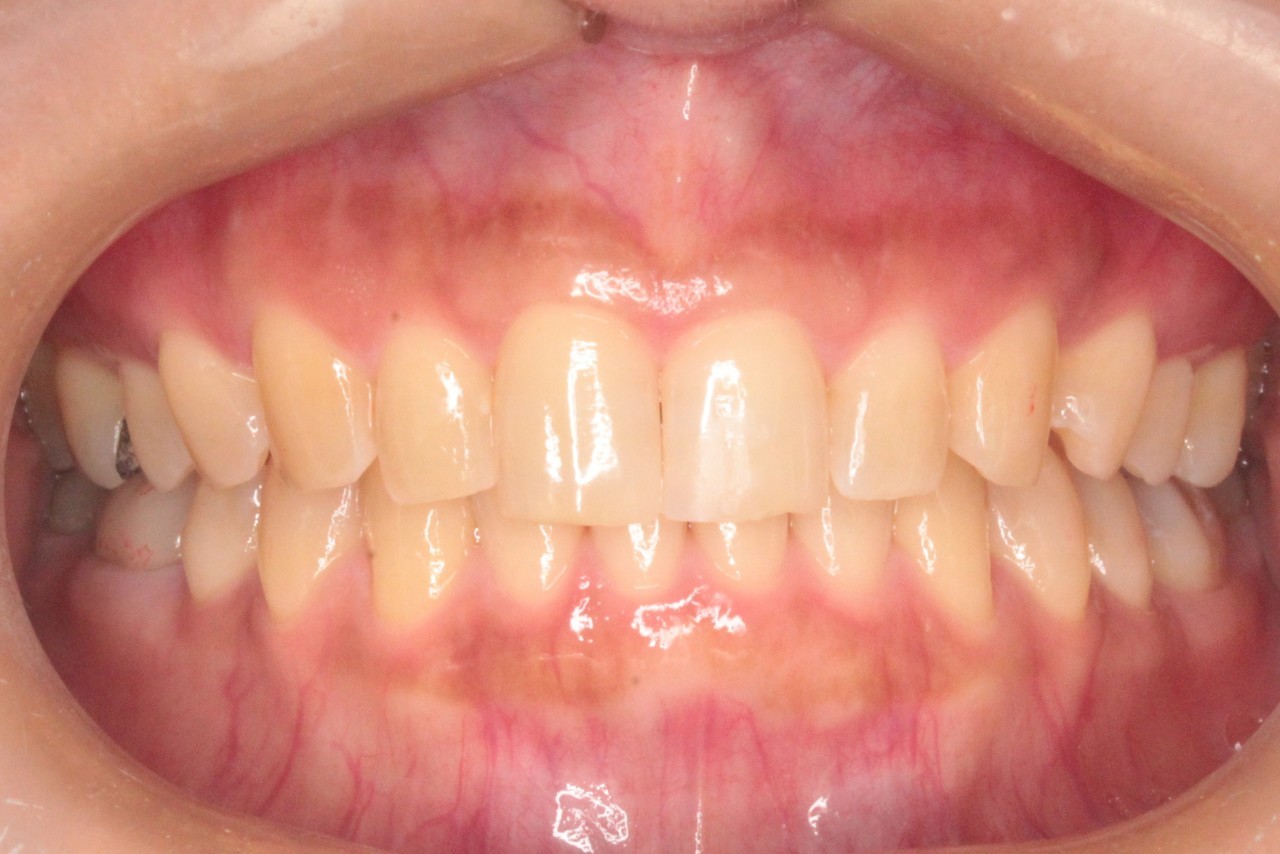

治療後

調布市の30代女性

主訴:歯と歯の間のすきまが気になる

使用装置:インビザライン

治療期間:約1.5年

治療費用:93.5万円(税込)

治療結果:空隙歯列が改善されました

※治療前の欠けている前歯は治療後に当院で修復しております

①の症例よりも前歯の離開度合いが強く

更に前歯が下方に挺出(ていしゅつ:歯の飛び出しのこと)しているので

圧下(あっか:歯を押し込むこと)をしっかり行うことが仕上がりに大きく影響します

また上の歯を配置するにあたり、下の歯も圧下する必要がありました

この上下の圧下が一番のポイントとなります